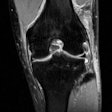

MRI can help assess additional damage from ACL injuries